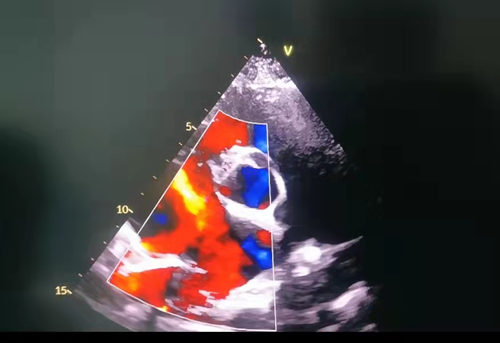

经详细检查,患儿缺损已有13mm,胸片提示右心明显扩大。经过儿童心血管科副主任徐振兴评估,发现该患儿具备介入手术条件,便带领先天性心脏病介入团队对手术方案进行了充分讨论,并针对术中和术后可能出现的病情变化进行了全面评估。1月26日上午,在DSA室、彩超室、麻醉科和护理部等部门的通力合作下,手术取得圆满成功。